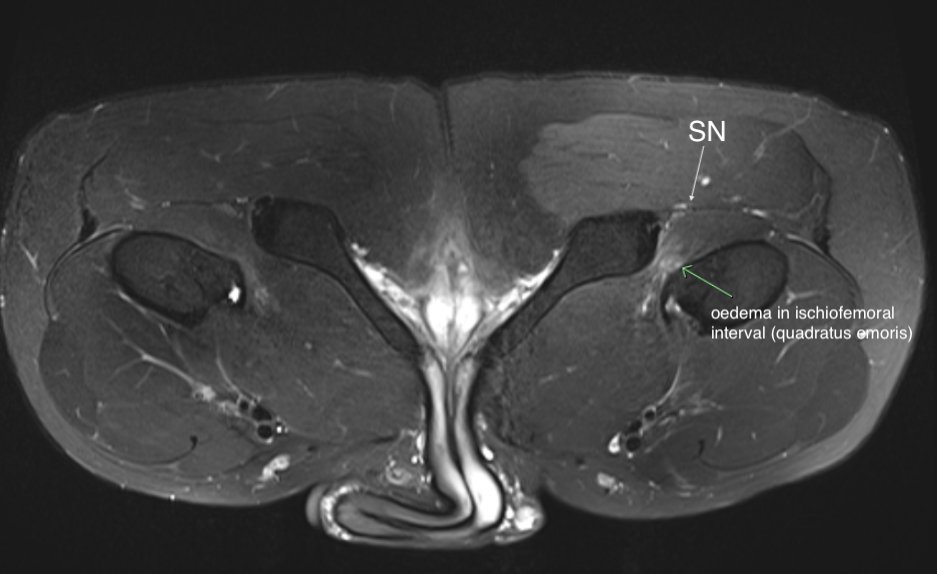

Consent✅ 1 year progressive severe (painless) L calf atrophy & weakness Medial bulk affected > lateral - see pic Affecting football performance Rolling over in bed onto R side - sudden 'spasms' in leg leg US - diffuse fatty atrophy of medial gastroc & soleus (vs R) EMG / NCS - severe L5 & S1 subacute chronic radiculopathy MRI - no herniated disc - but 5cm filum terminale lipoma (high signal on T1 seq, low on STIR). Also very low lying conus medullaris & tethered cord suggestive of spinal dysraphism (spina bifida occulta) Neurosurgical referral